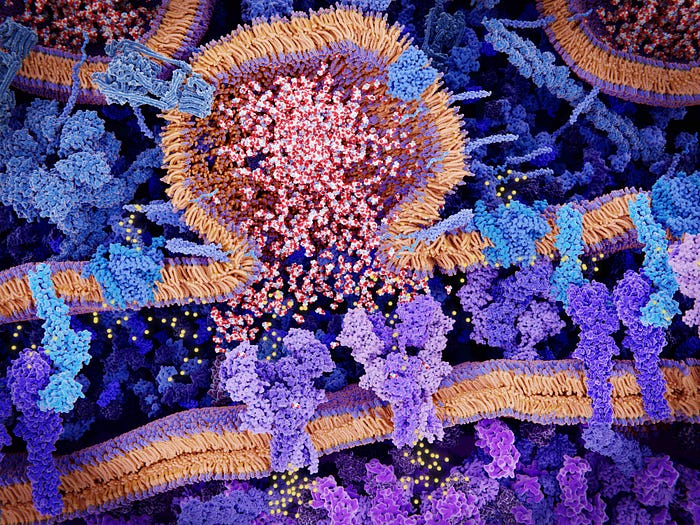

This was somewhat surprising, as the neurotransmitter glutamate has been shown to inhibit this cysteine uptake mechanism as part of its toxic effect on some neurons, and motor neuron diseases are linked to glutamate toxicity.

However, Wan’s result suggests that glutamate toxicity in motor neurons is not due to depleting cysteine, but rather due to other effects of glutamate, such as its interaction with glutamate receptors, as shown in the image below.